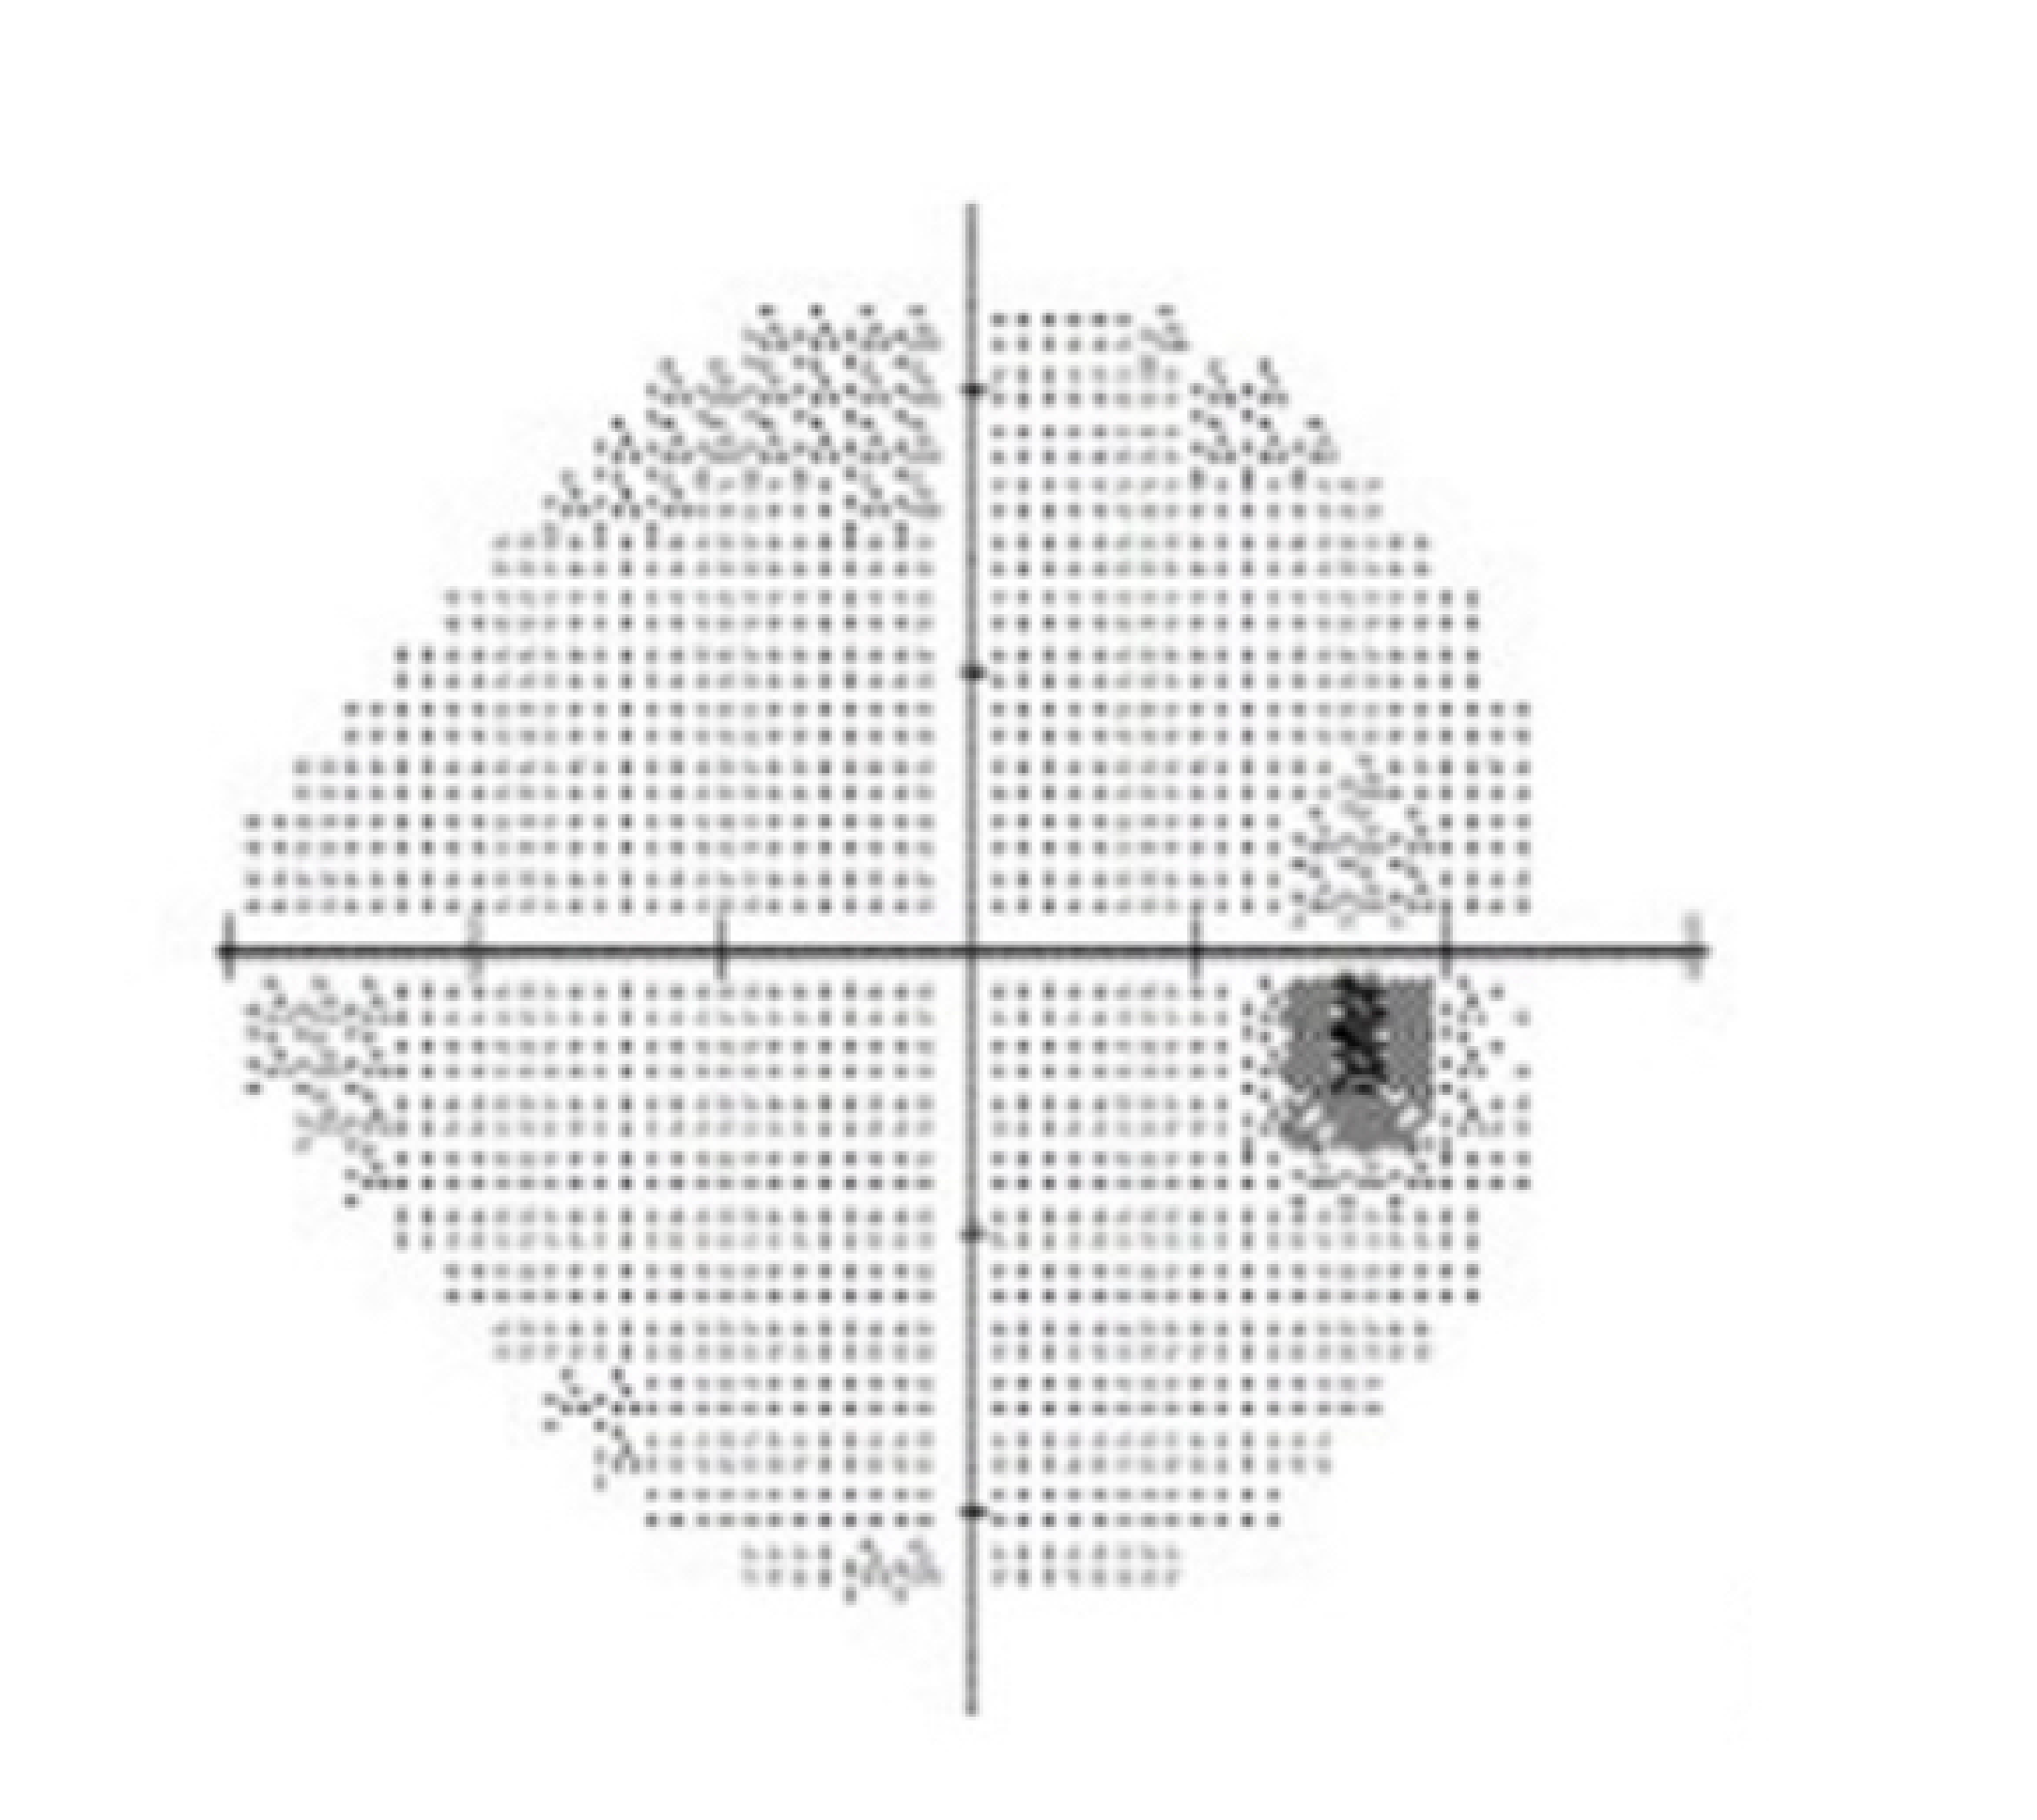

Glaucoma refers to the progressive destruction of vision nerve fibres that transmit signals to the vision processing centre of the brain. These nerve fibres are very sensitive to the pressure and blood supply within the eye. If both the eye pressure and blood supply are poorly regulated, these vital nerve fibres gradually die off, leading to permanent loss of vision.

The brain often fails to recognise that peripheral patches of vision are missing until the damage from glaucoma is significant. Although glaucoma is not curable, and vision already lost cannot be regained, it can be managed adequately to prevent any further vision loss or blindness.

Testing includes Visual filed assessment, Optic nerve fibre digital scans and photographic analysis, as well as eye pressure & structural assessment. If you have glaucoma, treatment can begin immediately to preserve your vision. It is a chronic condition that must be monitored for life.